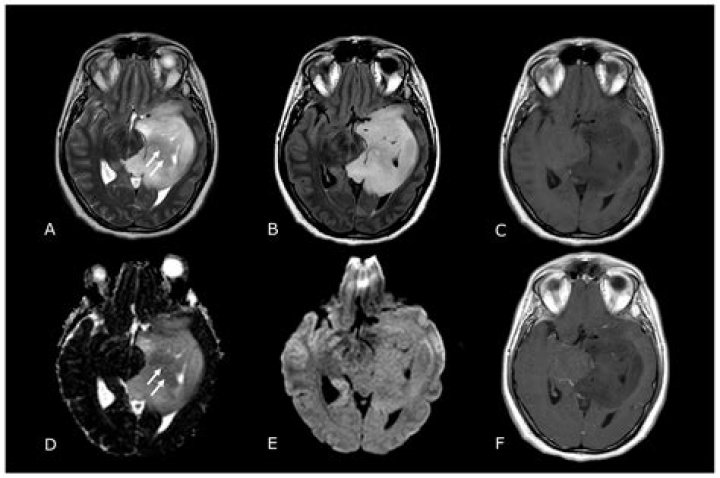

MRI can be used to detect brain tumors, traumatic brain injury, developmental anomalies, multiple sclerosis, stroke, dementia, infection, and the causes of headache.